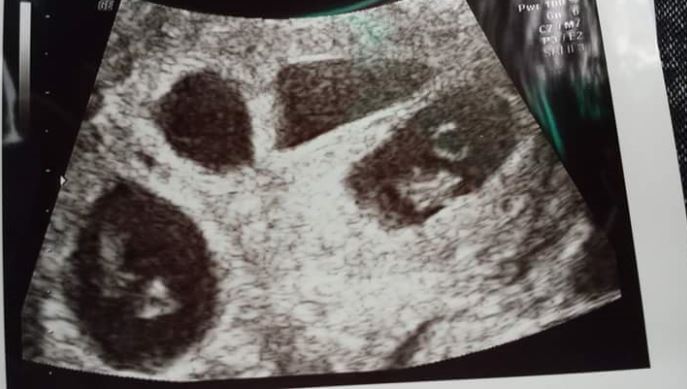

Tânăra a rugat-o pe mama ei să o însoțească la doctor, unde i s-a făcut o ecografie. În acel moment, doctorii au observat că fata era însărcinată cu… cvadrupleți. Adică avea patru bebeluși în abdomen. Fata este deja mama unei fetițe de 8 luni, iar acum va trebui să aibă grijă de cinci copii. Din fericire, familia ei este aproape de ea și este dispusă să o ajute cu orice va avea nevoie.

Cazurile de femei care au rămas însărcinate în mod natural cu cvadrupleți sunt extreme de rare.